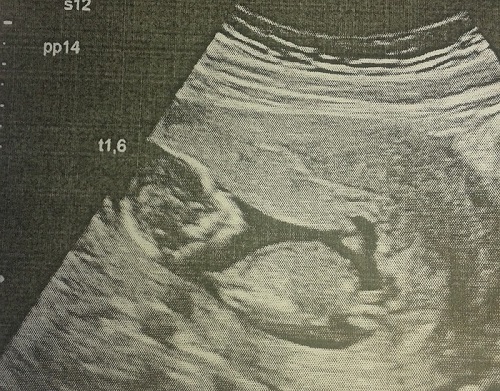

21 июля на сроке 19 и 4 мы сделали второе скрининговое УЗИ, на котором нам сказали, что у нас будет ДОЧЕНЬКА!!! Я расплакалась сразу же и не могла успокоиться)))))) Врач спросила, что меня пол не устраивает, а я рыдая говорю - наоборот!!! Малышка развивается отлично, опережая срок на недельку. Из плохого только амниотический тяж, который еще в 12 неделек видели, но сказали, что он не контактирует с плодом и это не страшно, растянется со временем. Плацента поднялась, на 1м УЗИ была в области внутреннего зева. Весим мы 360 г))). В общем из рисков у нас только возраст - 37 лет. Кровь на второй скрининг не сдавала, и не буду, потому как первый скрининг показал очень низкие риски и генетик сказала, что если 2е УЗИ все будет хорошо, то кровь можно не сдавать.

А это моя лялечка на 1м УЗИ 12 и 4))